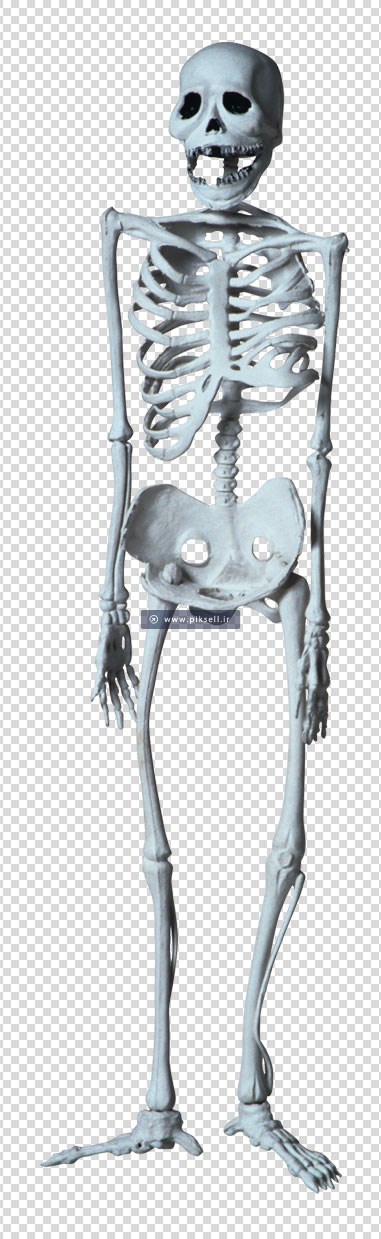

عکس اسکلت بدن انسان با کیفیت

دانلود عکس اسکلت انسان دانلود عکس آناتومی بدن خانم از پشت و جلو دانلود عکس باکیفیت جمجمه انسان.

عکس اسکلت بدن انسان با کیفیت. عکس اسکلت عکس اسکلت برای پروفایل عکس اسکلت انسان عکس اسکلت خفن عکس اسکلت بدن انسان با کیفیت عکس اسکلت بدن انسان عکس اسکلت ترسناک عکس اسکلت فانتزی عکس اسکلت فانتزی دخترانه پرچم عکس اسکلت. عکس با کیفیت اسکلت داخلی انسان و درد و گرفتگی در ناحیه استخوان زانو ویژه استفاده در امور تبلیغاتی و تجاری طراحی کاتالوگ بروشور و تراکت با موضوع پزشکی فیزیوتراپی ارتوپد دکتر روماتیسم فیریوتراپ طب فیزیکی. عکس اسکلت بدن انسان زن و مرد آناتومی ساتین 16 سپتامبر 2017. اسکلت داربست بدن است تمام قسمت های بدن روی اسکلت قرارگرفته اند بدن انسان از ۲۰۶ قطعه استخوان تشکیل شده است این استخوان ها طوری با نظم کنار هم قرار گرفته اند که انسان را قادر می سازد حرکات دقیقی داشته باشد.

اسکلت جمجمه و گردن انسان ستون فقرات آناتومی اسکلت جمجمه و گردن انسان ستون فقرات آناتومی تصویر با کیفیت را از لینک زیر می توانید دانلود کنید. ۱ مطلب با کلمه ی کلیدی عکس اسکلت بدن انسان با کیفیت ثبت شده است گالری نسیم جدید ترین و با کیفیت ترین عکس های مناسبتی. عکس با کیفیت آناتومی اسکلت بدن انسان و درد و دیسک در قسمت مهره های ستون فقرات کمر ویژه استفاده در امور تبلیغاتی و تجاری طراحی کاتالوگ بروشور و تراکت با موضوع بیمارستان ها و کلینیک ها و درمانگاه ها و مطب ها پزشکان و.